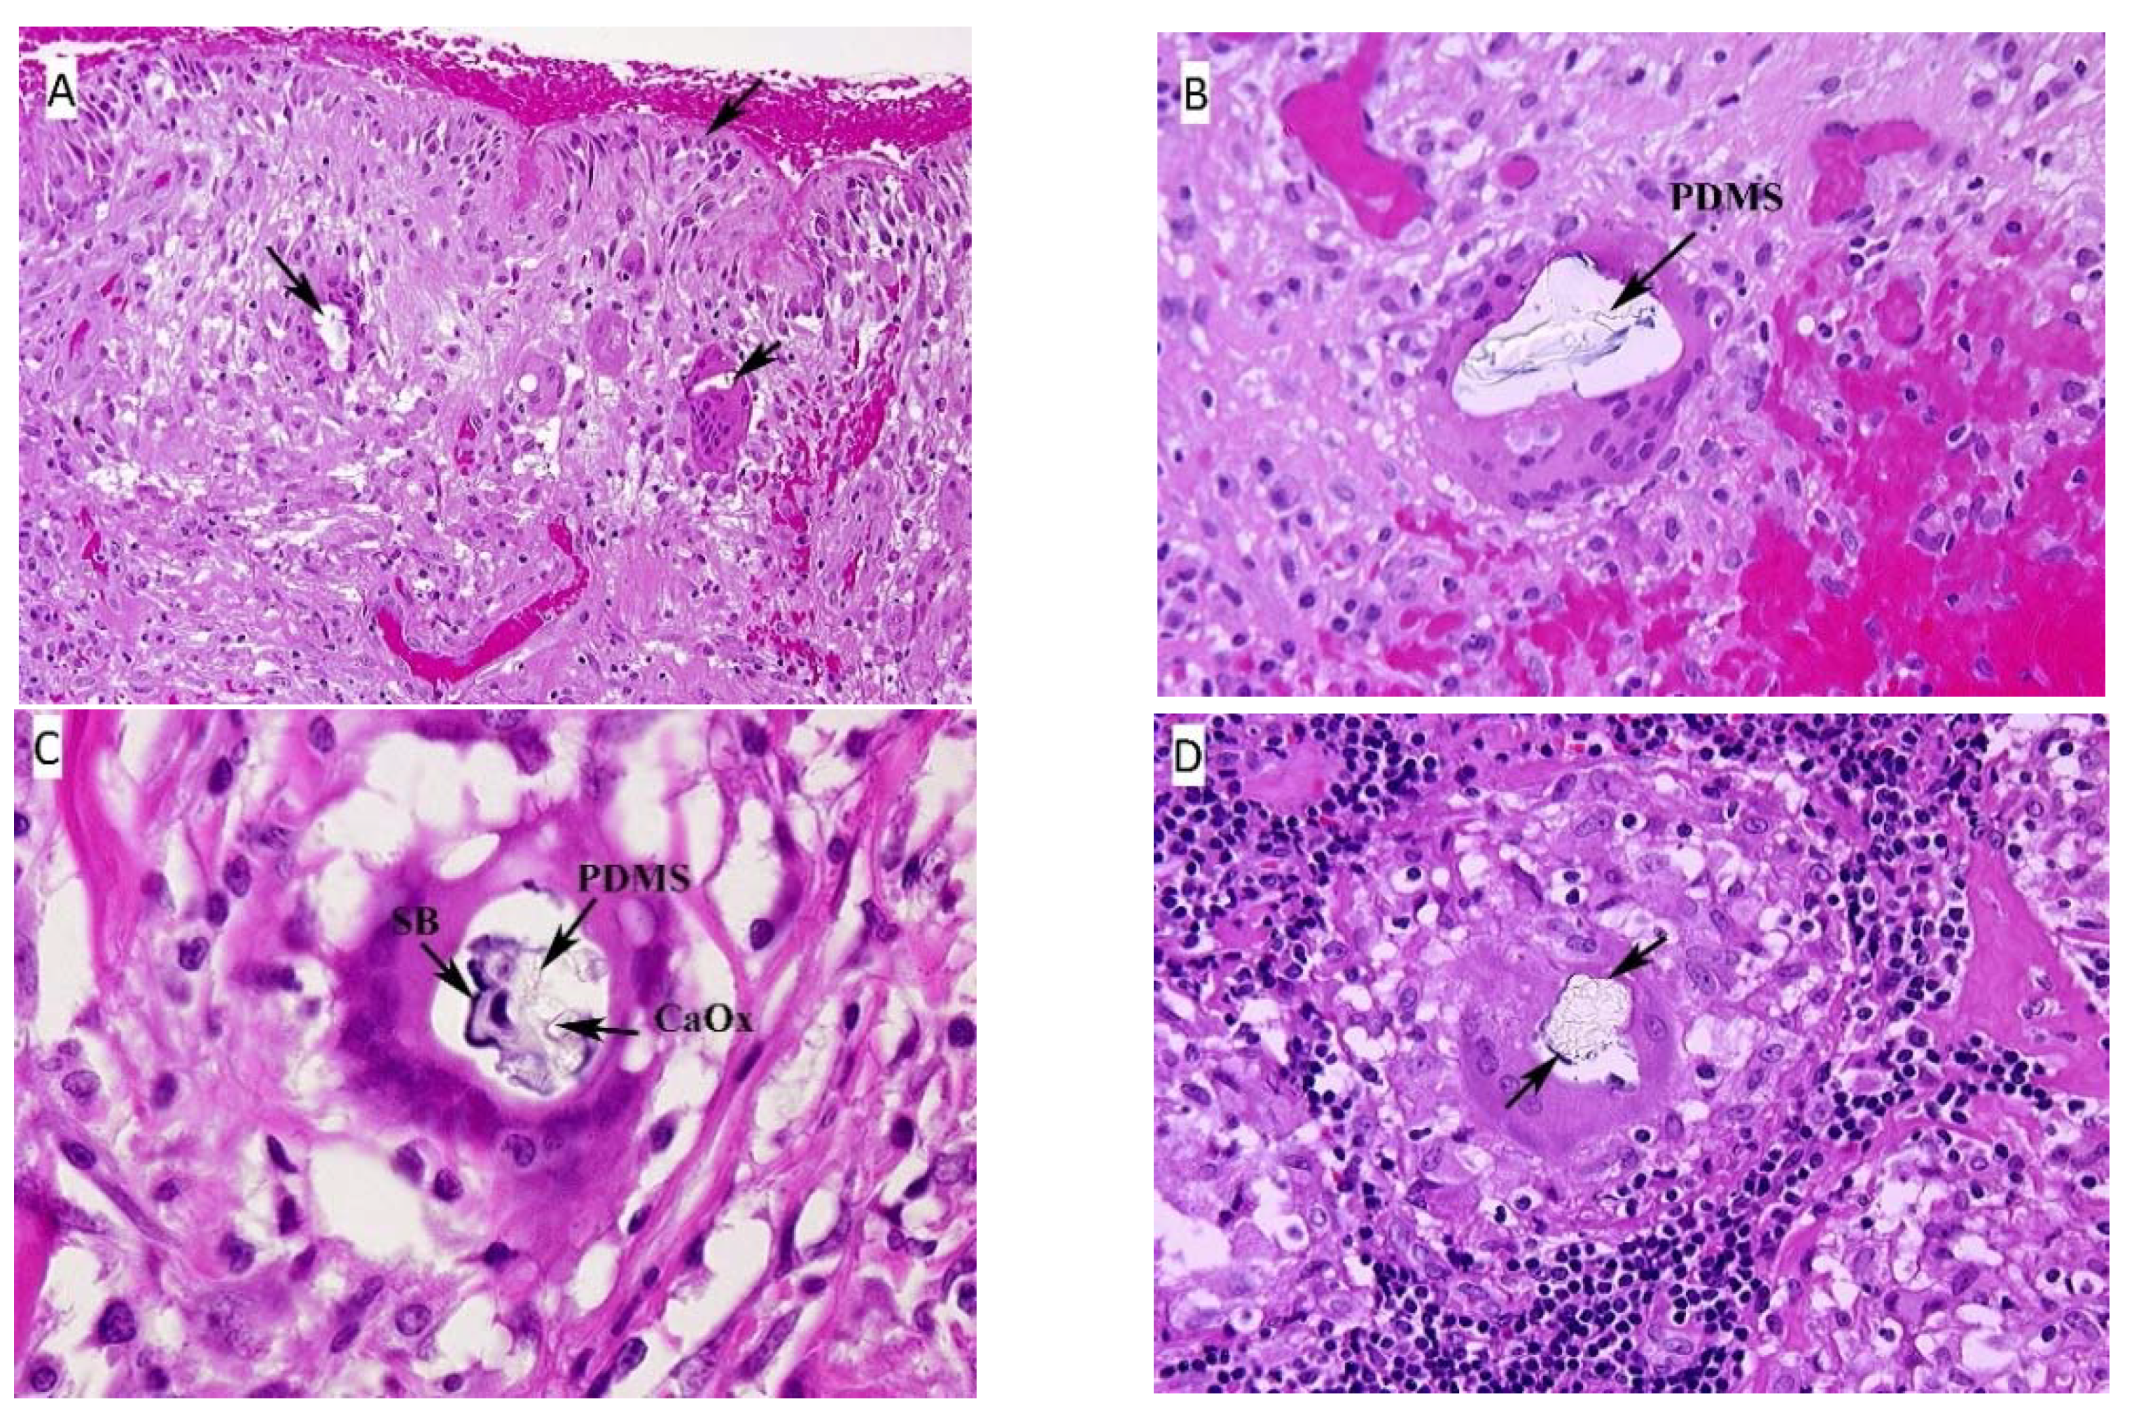

Hematoxylin-eosin (HE) stained sections showed a thick fibrous capsular wall with an inner lining of amorphous eosinophilic material, mononuclear cells and congested blood vessels forming a “pseudosynovium” (Figure 1A) [25]. There were numerous non-caseating granulomas, foreign body and Touton-type giant cells, and scattered chronic inflammatory cells within fibrous tissue. The granulomas were more prominent in the mid-section of the capsule wall, and their composition varied from a few epithelioid cells to large nodular aggregates surrounded by a thick fibrous collar. The foreign-body and Touton-type giant cells contained vacuoles with occasional Schaumann bodies, birefringent crystalline material, and clear refractile, non-birefringent material. The clear refractile material was confirmed as PDMS (Figure 1B) by confocal Raman microprobe analysis. Occasionally, all three of the inclusions were seen in the same giant cell (Figure 1C).

Figure 1.

(A) Fibrous capsule surrounding the implant, right. The surface of the tissue lies adjacent to the silicone breast implant and forms the “pseudosynnovium.” This pseudosynnovium is composed of amorphous eosinophilic material and mononuclear cells. Of note are several foreign body giant cells containing clear silicone gel. There is a chronic inflammatory infiltrate scattered among the fibroblasts, fibrous tissue, and collagen. (HE, 10×). (B) Fibrous capsule surrounding implant, right. A high-power view of the above tissue shows silicone gel within the giant cell that is embedded in fibrous tissue. There are also scattered chronic inflammatory cells, congested blood vessels, and surgical related hemorrhage. (HE, 100×). (C) Fibrous capsule surrounding implant, left. High power view of previous section. In the center of the multinucleated giant cell are fragments of Schaumann body (annotated on the image as SB), and refractile clear crystalline material consistent with calcium oxalate (annotated on the image as CaOx). (HE, 100×). (D) Axillary lymph node, left. There is clear refractile globular material in the center of the giant cell of the epithelioid granuloma consistent with silicone gel. In addition, fragments of a Schaumann body can be seen around the outer edge of the silicone gel. (HE, 100×). Arrows on the HE images, unless designated point towards areas of interest such as migrated PDMS.

3.1.2. Axillary Lymph Node, Left

The lymph nodes were almost totally replaced by non-caseating epithelioid granu- lomas of varying sizes and contained the same type of PDMS-based inclusions as seen in the fibrous capsule surrounding the implants (Figure 1D). Granulomas were also seen in the lymph node hilum.